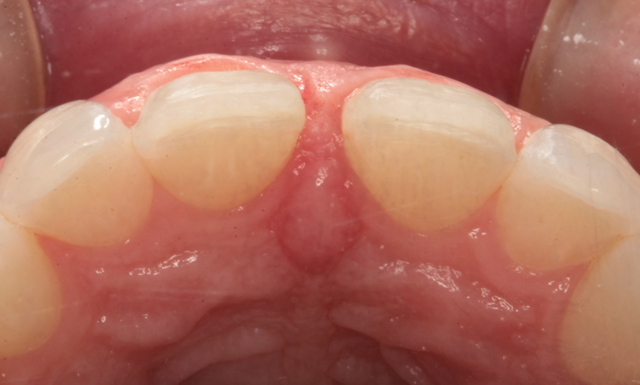

Figure 1 is a facial view of the first veneers in place. In the incisal view (Fig. 2), you can see that the veneers were used to close a central diastema. The reading from Vita Shade Light showed that the lateral incisors were 1M1 on the Vita 3D Shade Guide (Fig. 3).

Fig. 1 Fig. 2